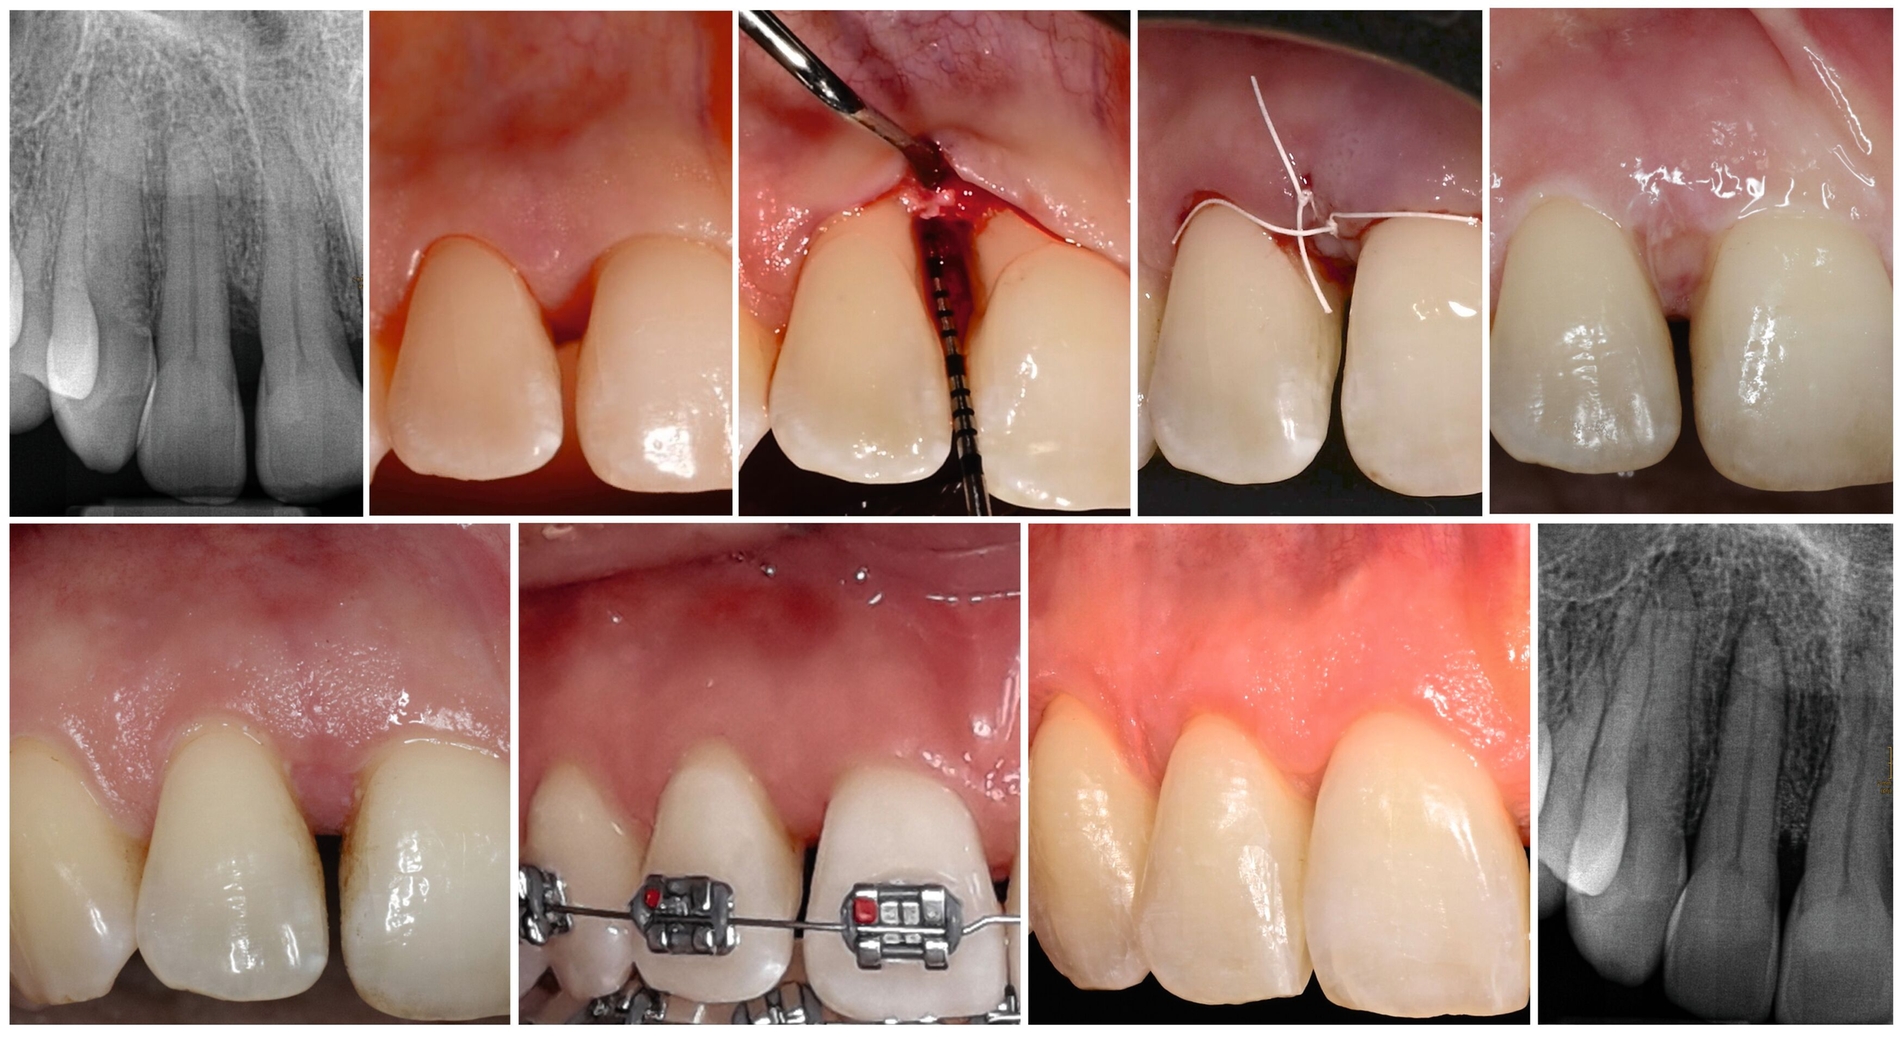

Zähne mit intraossären Defekten sind bei Patienten mit Parodontitis im Stadium IV häufig vorhanden (Abbildung 6). Diese Defekte sind nicht nur ein Komplexitätsfaktor für die Parodontaltherapie, sondern können auch die Ergebnisse der kieferorthopädischen Therapie beeinträchtigen, da Zahnbewegungen durch das regenerierte Gewebe geplant sein können (Abbildung 7). Wie in der zuvor veröffentlichten S3-Leitlinie für die Parodontalbehandlung von Parodontitis-Patienten in den Stadien I–III [Sanz et al., 2020] berichtet, sollten diese intraossären Defekte während der dritten Stufe der Parodontaltherapie durch chirurgische parodontale regenerative Eingriffe behandelt werden. Nach dieser Therapie ist es wichtig zu verstehen, ob kieferorthopädische Zahnbewegungen bei diesen betroffenen Zähnen sicher durchgeführt werden können und welches das angemessene Zeitintervall zwischen dem chirurgischen Eingriff und dem Beginn der aktiven kieferorthopädischen Zahnbewegungen ist.

Die Daten der drei systematischen Reviews [Kloukos et al., 2022; Martín et al., 2022; Papageorgiou et al., 2022] wurden aus 16 Studien mit insgesamt 683 Patienten gewonnen: drei RCTs, zehn prospektive und drei retrospektive Fallserienstudien. Zwei RCTs wurden mit einem hohen Risiko der Verzerrung und das RCT, in dem eine frühzeitige mit einer verzögerten kieferorthopädischen Behandlung verglichen wurde [Jepsen et al., 2021], mit einem geringen Verzerrungsrisiko bewertet. Von den verbleibenden 13 Studien wurden acht mit kritischem Verzerrungsrisiko, vier mit hohem und eine Studie mit mittlerem Risiko bewertet. Eine retrospektive Kohortenstudie mit 48 Patienten [Tietmann et al., 2021] berichtete über eine mittlere PPD-Reduktion von 2,5 mm und einen mittleren RBL-Gewinn von 4,7 mm nach zwölf Monaten. Ein „Pocket Closure“ (PPD ≤ 4 mm) wurde bei 87 Prozent der Defekte erreicht. Die Ergebnisse des RCT, der den frühen mit dem späten Beginn der kieferorthopädischen Behandlung nach der parodontalen Regenerationsbehandlung verglich, zeigten eine potenziell positive Wirkung der frühen kieferorthopädischen Behandlung, da keine statistisch signifikanten Unterschiede in Bezug auf den CAL-Zuwachs (5,4 mm [SD=2,1] für die frühe und 4,5 mm [SD=1,7] für die späte kieferorthopädische Behandlung) oder die PPD-Reduktion (4,2 mm (SD=1,9) in der frühen Gruppe gegenüber 3,9 mm (SD=1,5) in der späten Gruppe (p > 0,05)) beobachtet wurden. In ähnlicher Weise trat ein „Pocket Closure“ (PPD ≤ 4 mm) bei 91 Prozent der früh OT-behandelten Zähne gegenüber 85 Prozent bei der späten OT auf [Jepsen et al., 2021].

Die eingeschlossenen Studien stimmten allgemein darin überein, dass bei Patienten mit schwerer Parodontitis (Stadium IV oder gleichwertig) und mit Vorhandensein von parodontalen Knochendefekten die Kombination einer regenerativen Parodontalbehandlung mit einer kieferorthopädischen Therapie die parodontalen Ergebnisse positiv beeinflusst. Darüber hinaus scheinen die Vorteile einer frühzeitigen kieferorthopädischen Therapie (ähnliche Ergebnisse bei deutlich verkürzter Gesamtbehandlungsdauer) die potenziellen Risiken zu überwiegen.

Neuere Untersuchungen, die nach Fertigstellung der europäischen Leitlinie [Herrera et al., 2022] publiziert worden sind, belegen die Langzeitstabilität einer parodontal-regenerativ/kieferorthopädischen Therapie [Tietmann et al., 2023], die Überlegenheit einer frühzeitigen OT hinsichtlich des CAL-Gewinns nach 24 Monaten und die positiven Auswirkungen einer kombinierten Therapie auf die mundgesundheitsbezogene Lebensqualität der Patienten [Jepsen et. al., 2023].

2. Die zirkumferentielle Fibrotomie der suprakrestalen Parodontalfasern wurde als zusätzliches chirurgisches Verfahren vorgeschlagen, um die Stabilität nach einer Korrektur stark gedrehter Zähne zu verbessern, oder als Eingriff zur Verbesserung des Attachmentniveaus während der kieferorthopädischen Intrusion. Der Einsatz der Fibrotomie als Ergänzung zur kombinierten Parodontal-/Kieferorthopädie-Behandlung war mit Vorteilen bei CAL und RBL, aber nicht bei PPD verbunden (Abbildung 9). Allerdings wiesen die beiden RCTs in mindestens zwei Bereichen ein hohes Verzerrungsrisiko auf.